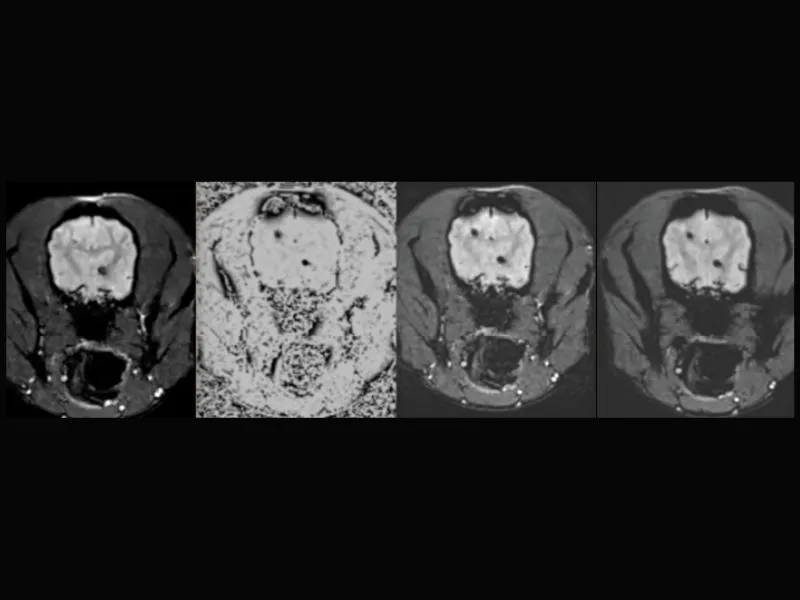

Supreme vet-mr – DWI of a cerebral infarction in a dog